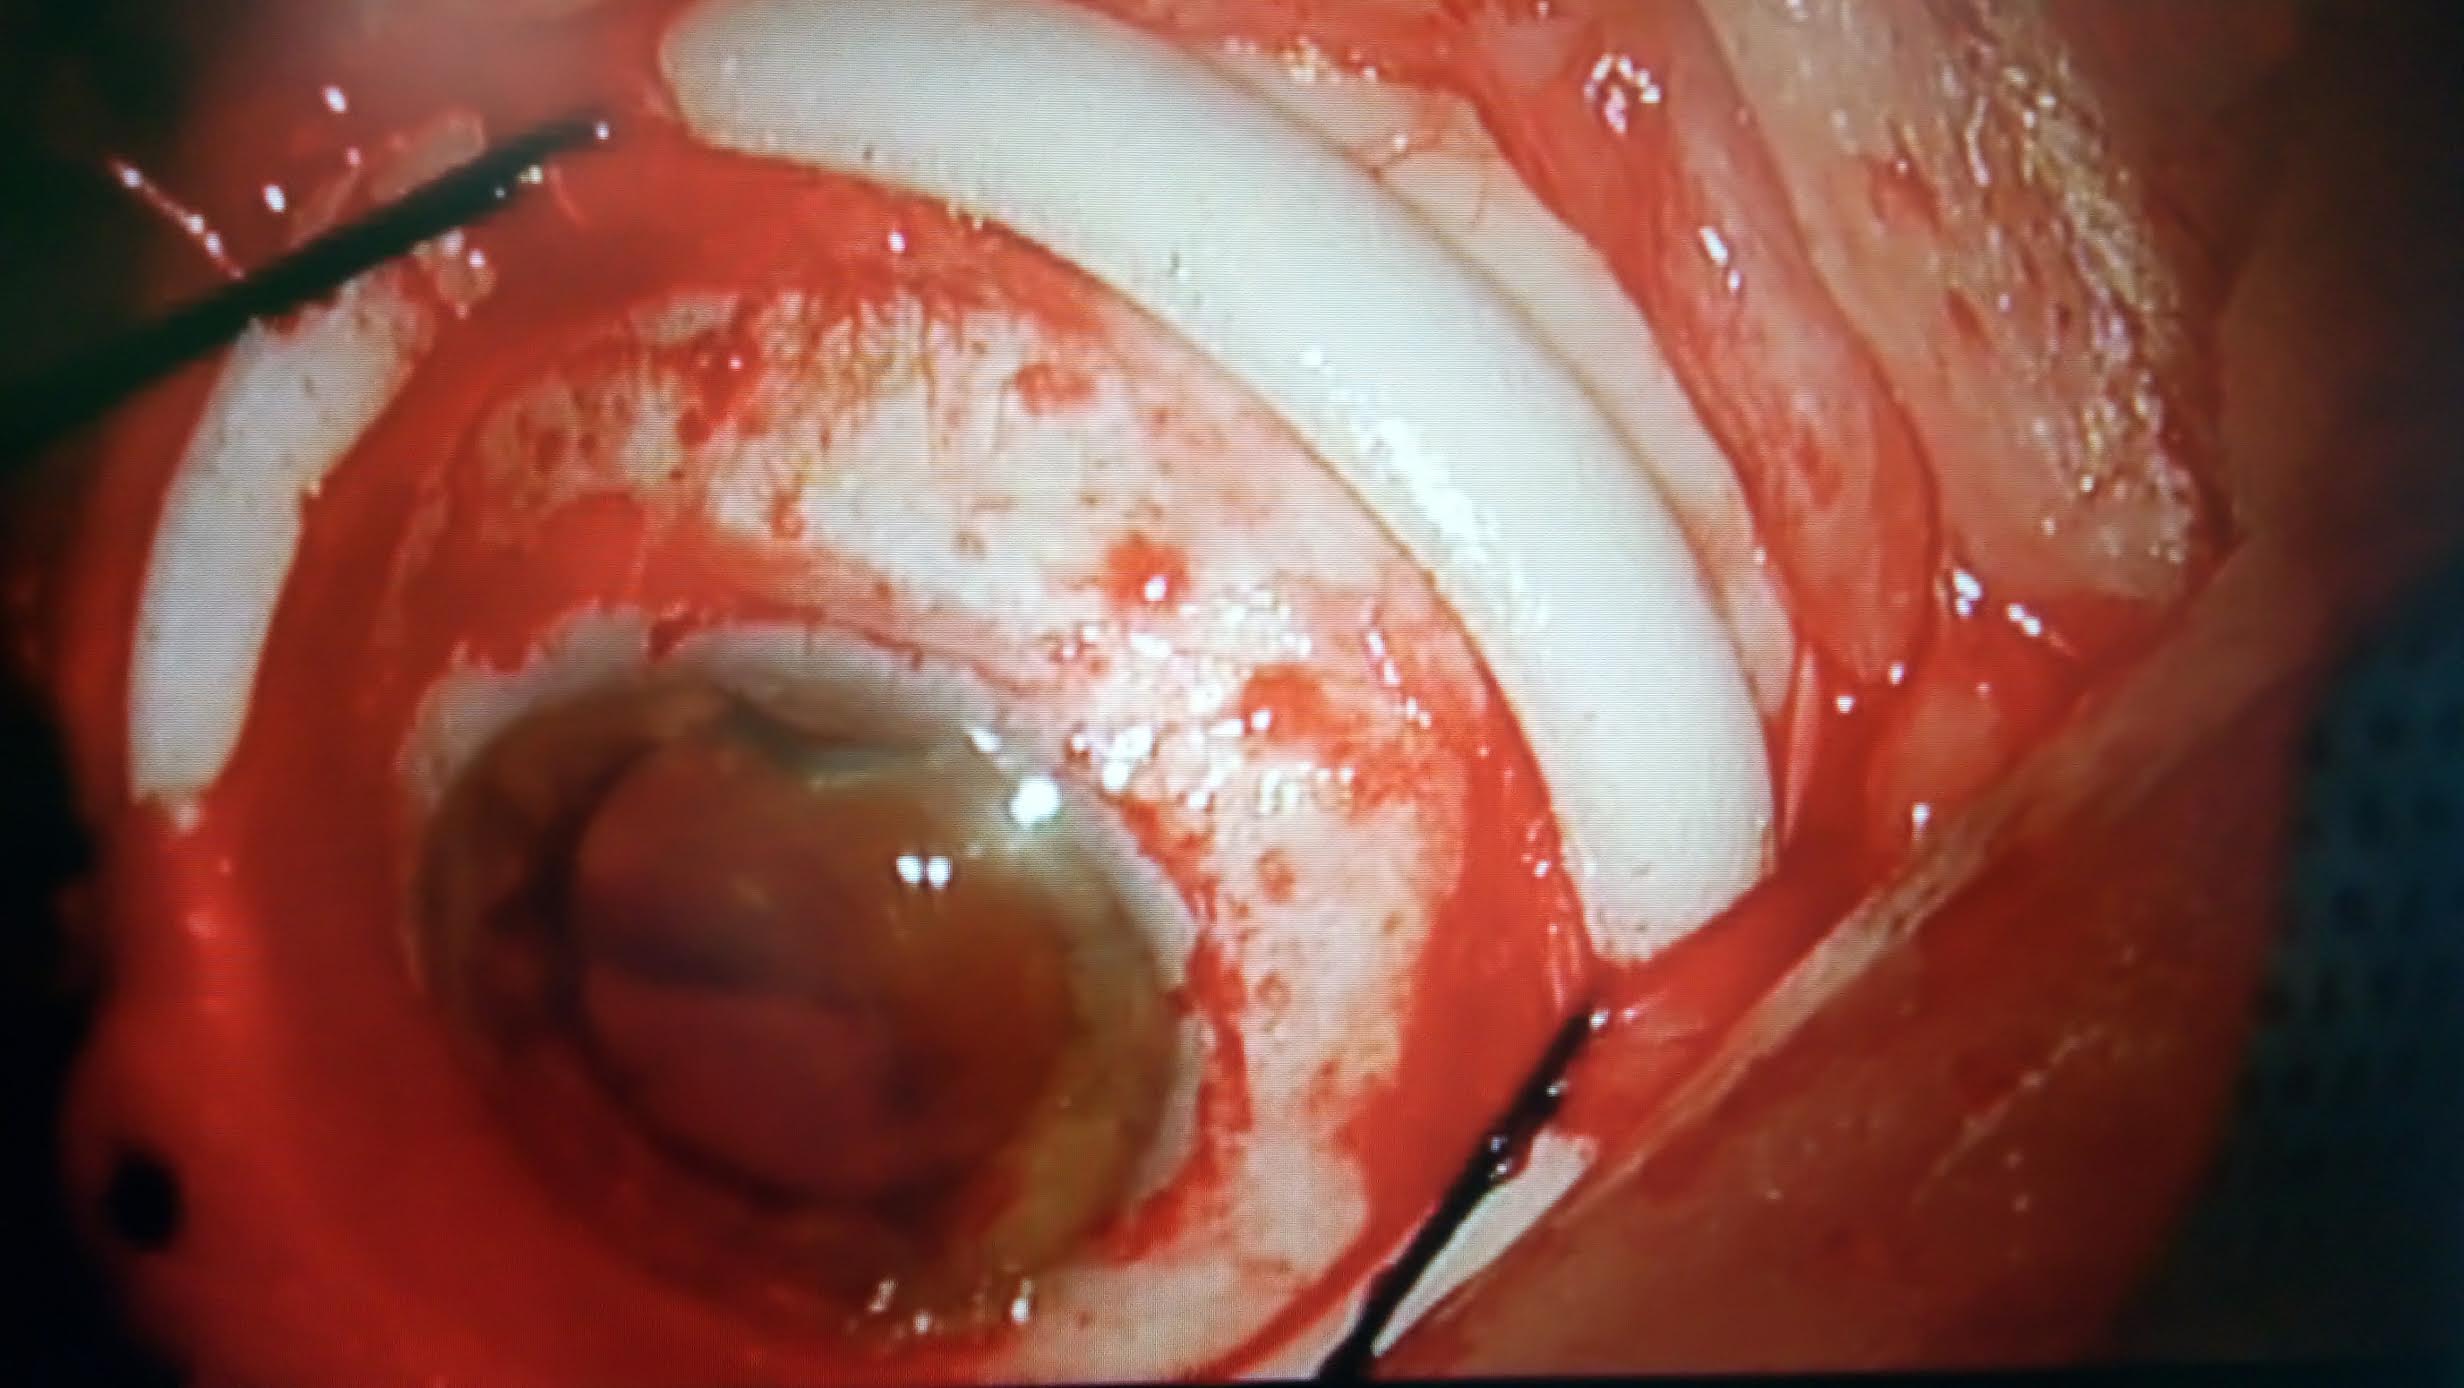

10 Intervento di chirurgia episclerale per distacco di retina

Paziente di 67 anni riferisce forte calo visivo nell'occhio destro da alcuni giorni, l'obiettività oculistica era la seguente:

Visus 2/50 non migliorabili con lenti

tono 11 mmhg

biomicroscopia nella norma

fundus: distacco di retina macula off (coinvolgente anche la macula) da ore 3 a ore 9 circa con duplice rottura retinica ore 6 circa

Effettuata chirurgia episclerale (cerchiaggio)

1) Peritomia congiuntivale su 360° isolamento dei muscoli retti e posizionamento dei fili di trazione) foto 1

2) Posizionamento di fibra ottica per esplorazione del fundus con sistema biom foto  2

3) Localizzazione delle rotture retiniche e criotrattamento foto 3

4) Cerchiaggio con spugna in silicone foto 4

5) Puntura evacuativa e drenaggio del fluido sottoretinici foto  5

6) Controllo indentazione delle rotture foto 6

7) Sutura congiuntivale foto 7

Il decorso post operatorio è stato regolare